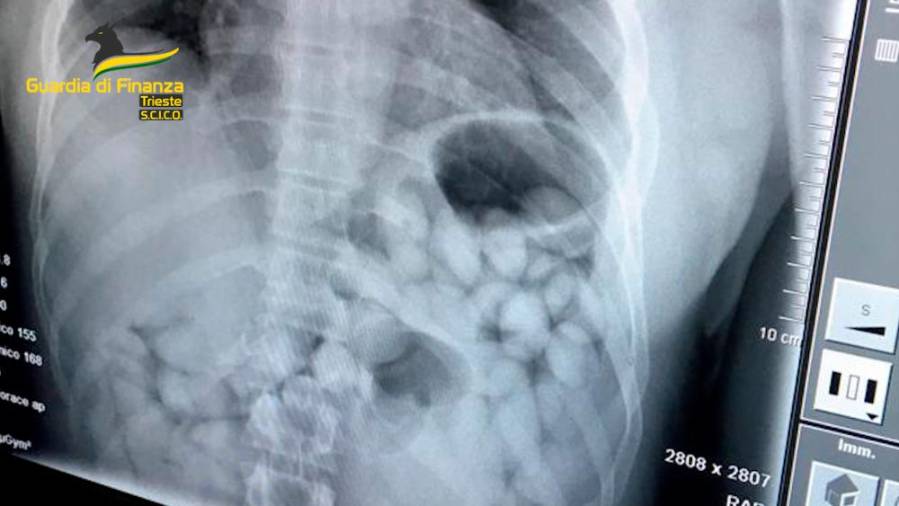

Drogo so prevažali v kapsulah, ki so jih pogoltnili (FINANČNA POLICIJA)

Kapsule na rentgenskem posnetku (FINANČNA POLICIJA)